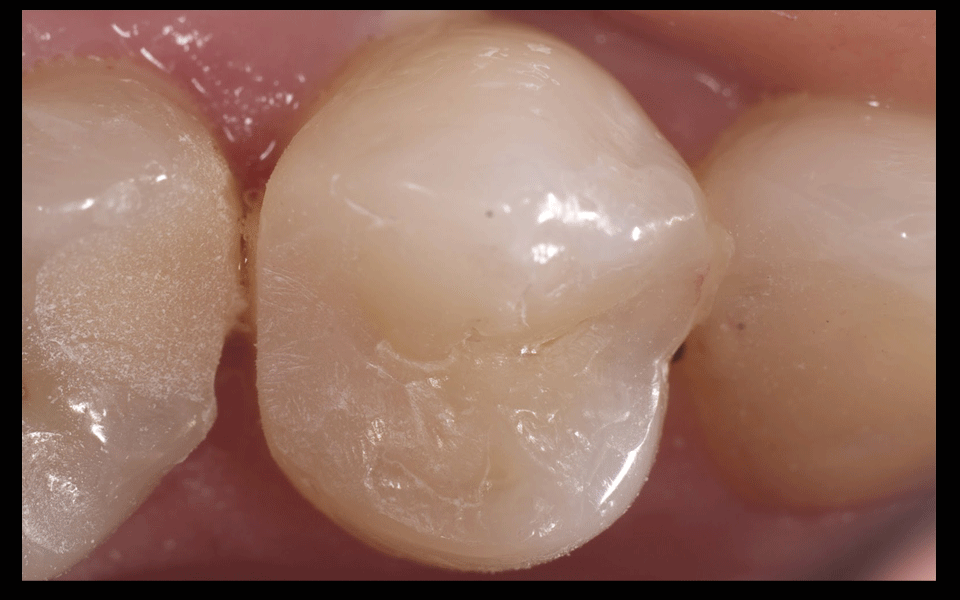

Краевое прилегание пломбы – это качество соединения пломбы с тканями зуба. Именно краевое прилегание пломбы обеспечивает герметичность зуба. Пломба, которая идеально плотно прилегает к зубу простоит очень долго. Под микроскопом значительное увеличение позволяет проконтролировать герметичность пломбы, идеально пришлифовать пломбу к зубу и гарантировать ее долговечность.

Установленная под микроскопом пломба простоит в 2 раза дольше, ведь врач под увеличением проверит качество прилегания пломбы к зубу, а значит обеспечит ее герметичность. Любое воспаление под пломбой возникает при нарушении ее герметичности. С применением микроскопа пломба содержит большее количество слоев пломбировочного материала. Под значительным увеличением врач аккуратно слой за слоем восстановит разрушенный зуб повторяя структуру ткани идентично живому зубу, внутри будет более прочный материал для распределения нагрузки, а снаружи более прозрачный для естественной белизны и преломления света. Диагностика кариеса под микроскопом обладает высокой точностью. При помощи микроскопа врач не пропустит начальный кариес, увидит кариес в стадии пятна, обнаружит трещины и сколы. При ранней диагностики кариеса без сверления и без бормашины можно остановить кариес специальными изоляционными пломбировочными материалами. Зубу будет возвращена герметичность, а вы никогда не узнаете, что такое зубная боль.